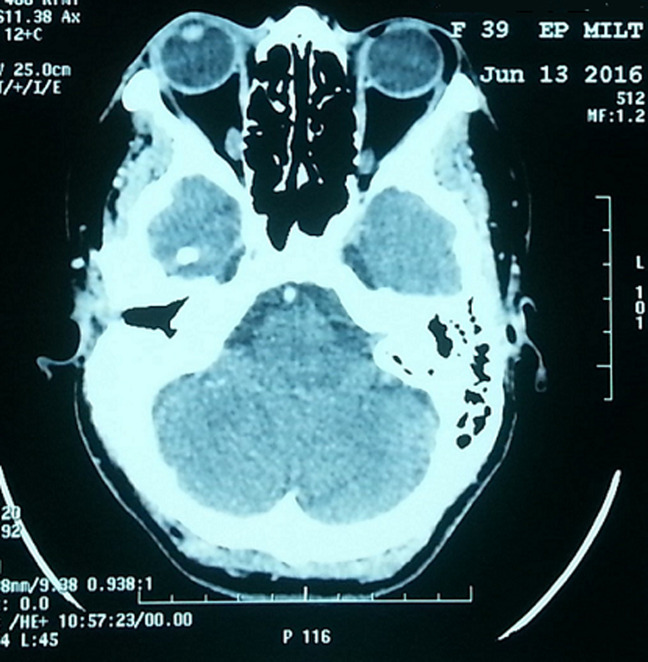

Subcutaneous lipomas are very common tumors preferentially occurring in the neck and trunk. Although rare and unusual, they can occur in other parts of the body. Then they should be suspected in patients with subcutaneous swellings. We here report 3 cases of lipomas occurring in rare sites, detailing diagnosis and treatment. They occurred in the interdigital web space of the hand, toe and lateral canthus of the eye.